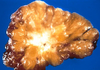

Medullary Carcinoma:

- Mammographic findings

- Gross findings

-

Mammographic findings

- Oval circumscribed mass

- Can be mistaken for fibroadenoma

-

Gross findings

- Soft, fleshy

- Circumscribed border

- Lobulated, bulging cut surface